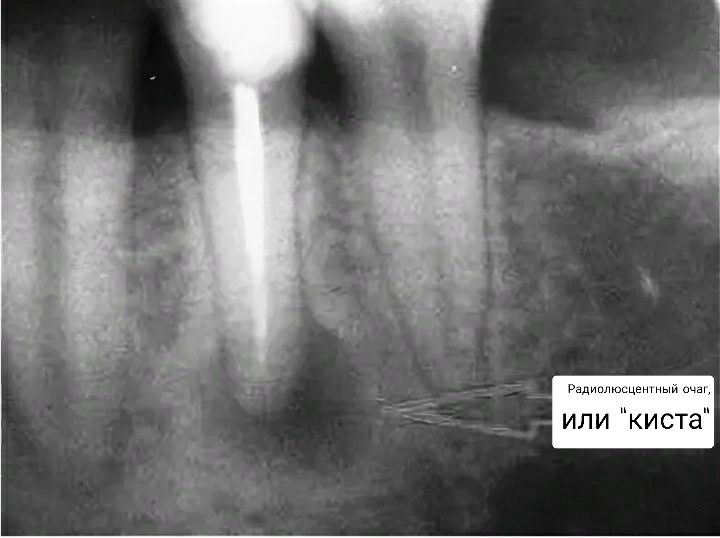

1. Часто лечение проводят без рентген-снимка. Это в корне неверная тактика. Без снимков полости рта врач не увидит зону поражения кариесом. Также невозможно сказать, дошёл ли процесс до пульпы. По рентгену можно оценить состояние костной ткани, состояние корней зубов (есть ли изменения в их периапикальной части).